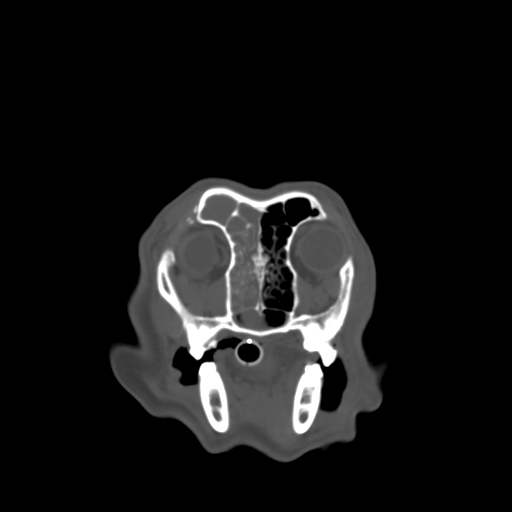

VetTom 8 provides diagnostic quality Computed Tomography (CT) images in a small mobile package. The system is capable of providing at 25 cm field-of-view with high contrast to noise giving you diagnostic confidence for soft-tissue disease and injury.

The modern Through-Silicon-Via (TSV) stacked CT detectors provide high-resolution images with low noise and high contrast, while the 40 cm gantry and 30 cm field-of-view provide additional space and information for your diagnostic needs versus VetTom 8.

The VetTom 32 has a powerful 40 kW generator, 85 cm gantry, 60 cm field-of-view, scans using proprietary batteries and can be moved to where you need imaging, especially when it may be difficult to move the patient.